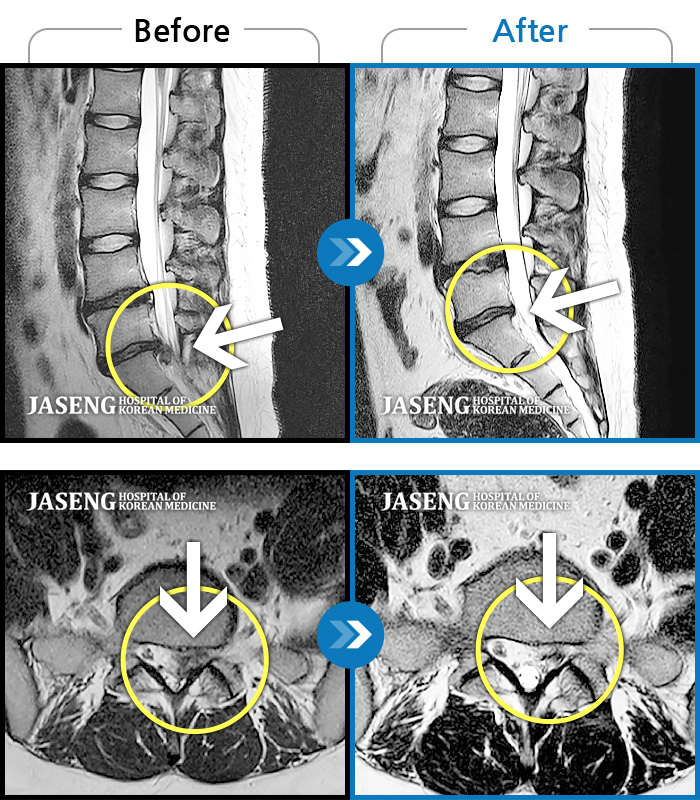

허리디스크

천안 · 윤영웅 원장

허리와 좌측 다리 통증, 저림이 심해요.

촬영시기

2021.10.25 ~ 2022.05.21

2022.05.24

조회수 150